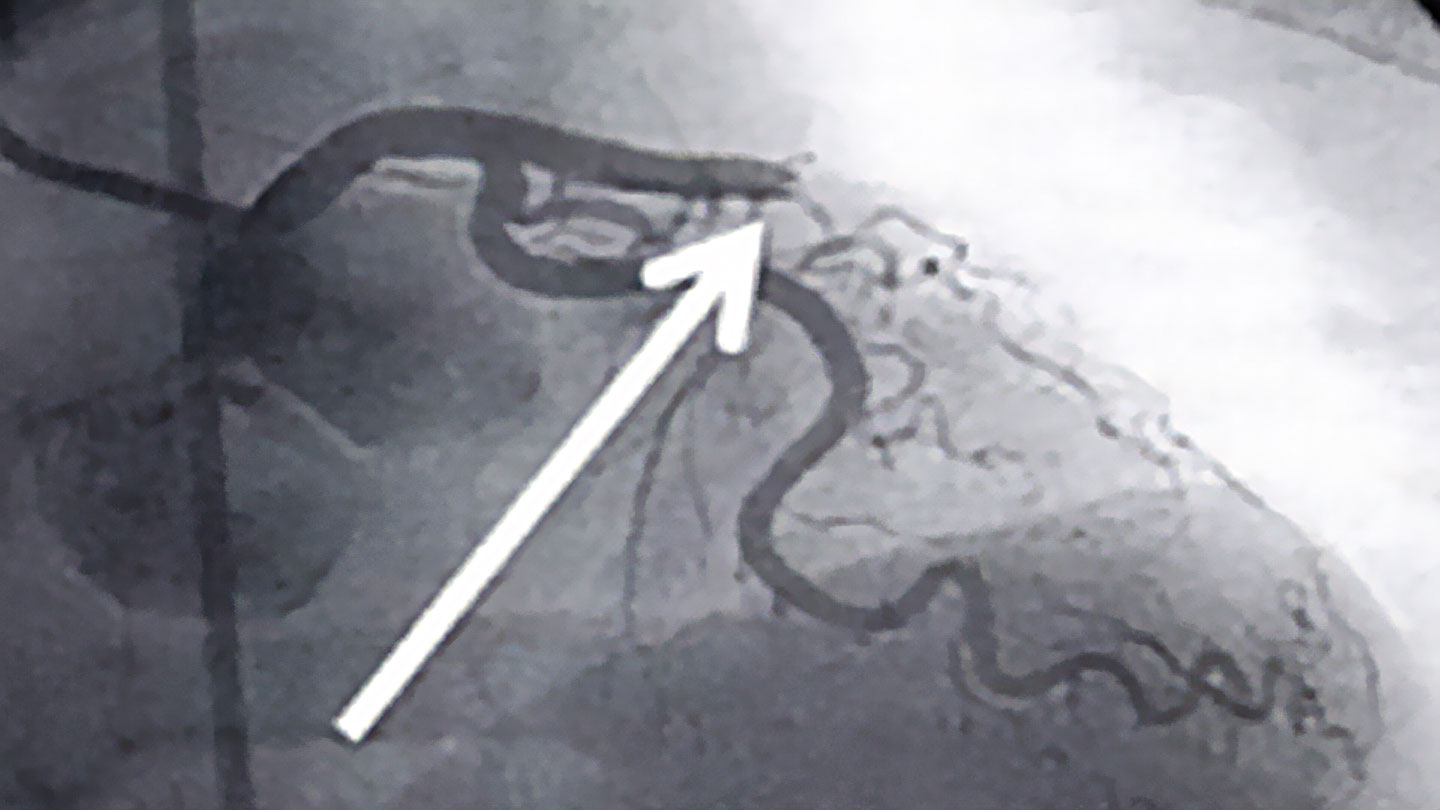

Every second counts in the event of a heart attack. The faster a blocked coronary artery is reopened, the greater the likelihood that no long-term consequences such as cardiac insufficiency or cardiac arrhythmia will remain. The gold standard in such situations is a cardiac catheterisation, which can be used to reopen coronary arteries by means of a balloon and the placement of a stent. This allows the heart muscle to receive sufficient oxygen to regenerate.

© herzmedizin.berlin